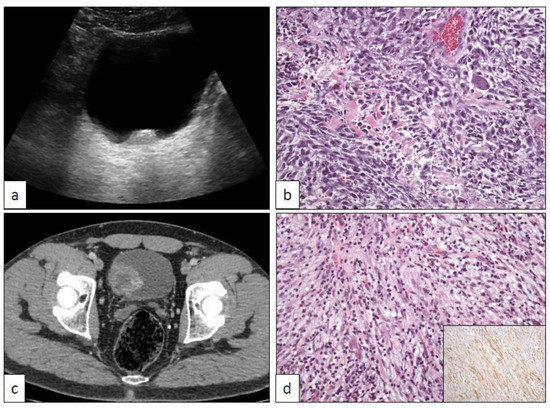

6. Xantho-Granulomatous Inflammation (XI)